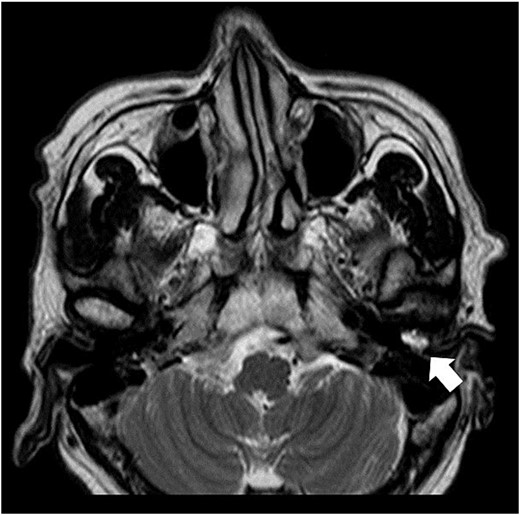

A 62-year-old man presented with a left external auditory canal obstruction and a smooth swelling on the anterior wall. Audiological exams showed no abnormalities, and no otorrhea was observed. Medical history included emphysema, duodenal cancer, and gastric ulcer. The patient was diagnosed with an external auditory canal cyst and underwent cystectomy at the Department of Otorhinolaryngology of our hospital in February 2017. Histopathological examination revealed a cystic lesion without epithelial lining, diagnosed as a ganglion-like lesion. In May of the same year, the swelling was observed again (Fig. 1). The patient was referred to our department for further investigation because computed tomography (CT) revealed enlargement of the left mandibular head (Fig. 2). Clinical findings at the time of consultation included symmetrical facial appearance and a maximum range of motion of 55 mm in the mandible. Upon opening the mouth, crepitus was observed in the left TMJ; however, no restriction of the lateral or anterior movement of the mandible or occlusal deviation was observed. There was no pain in opening the mouth or tenderness in the TMJ. The anterior wall of the left external auditory canal was swollen, with elasticity and no mobility. T2-weighted magnetic resonance imaging revealed an internal high-signal mass in the external auditory canal (Fig. 3).

Axial T2-weighted MRI. MRI image shows a high-signal area in the left external auditory canal.